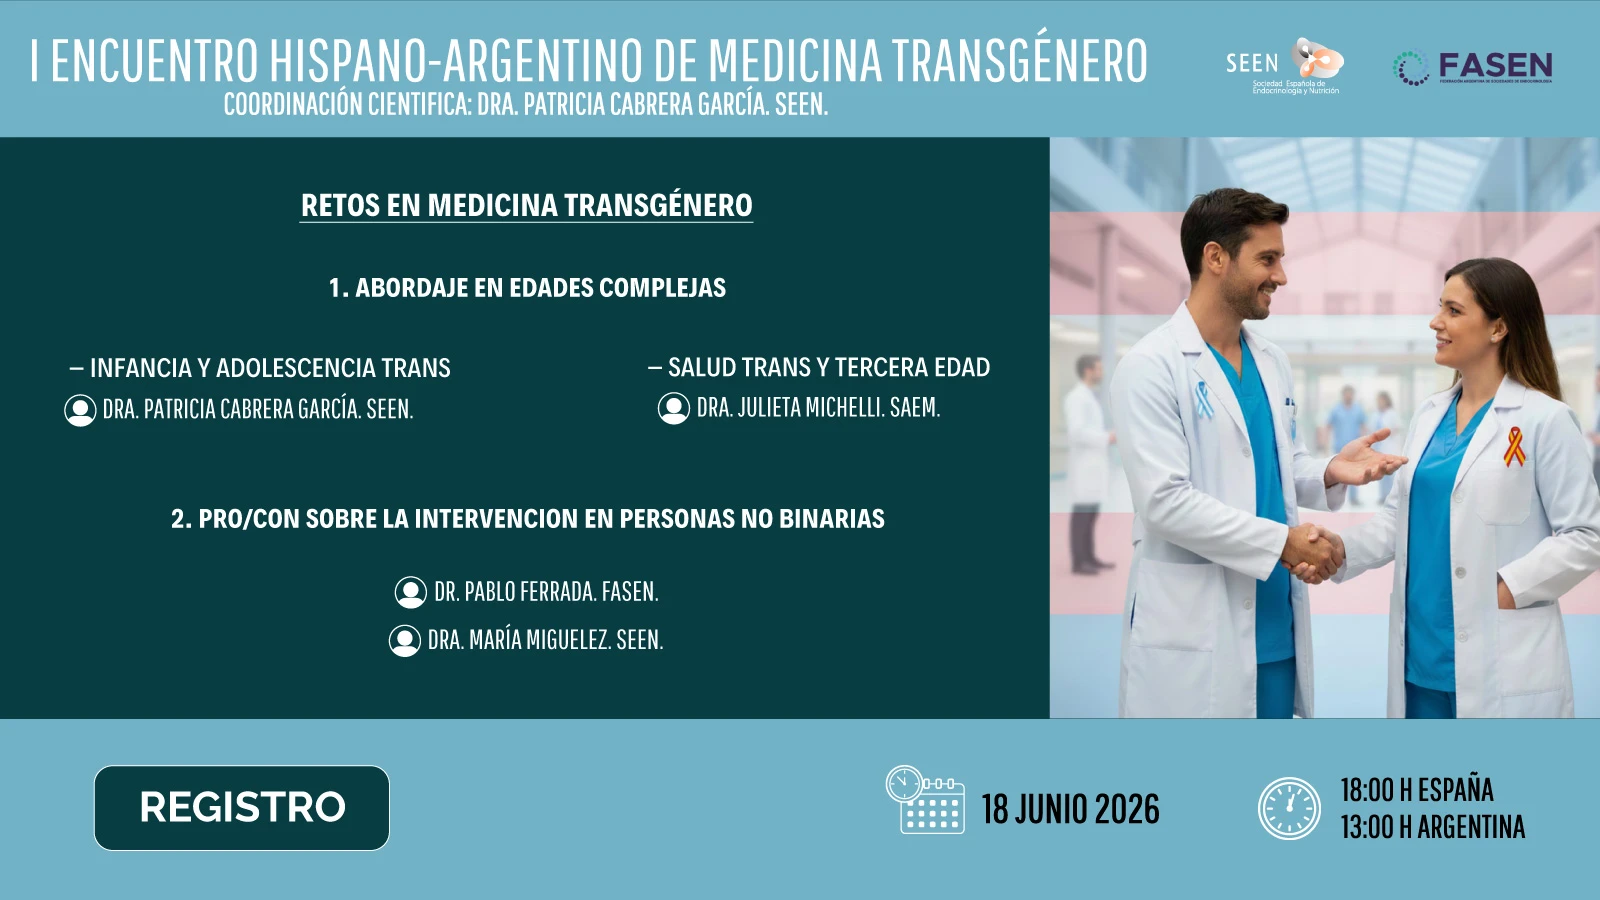

Auspicios FASEN